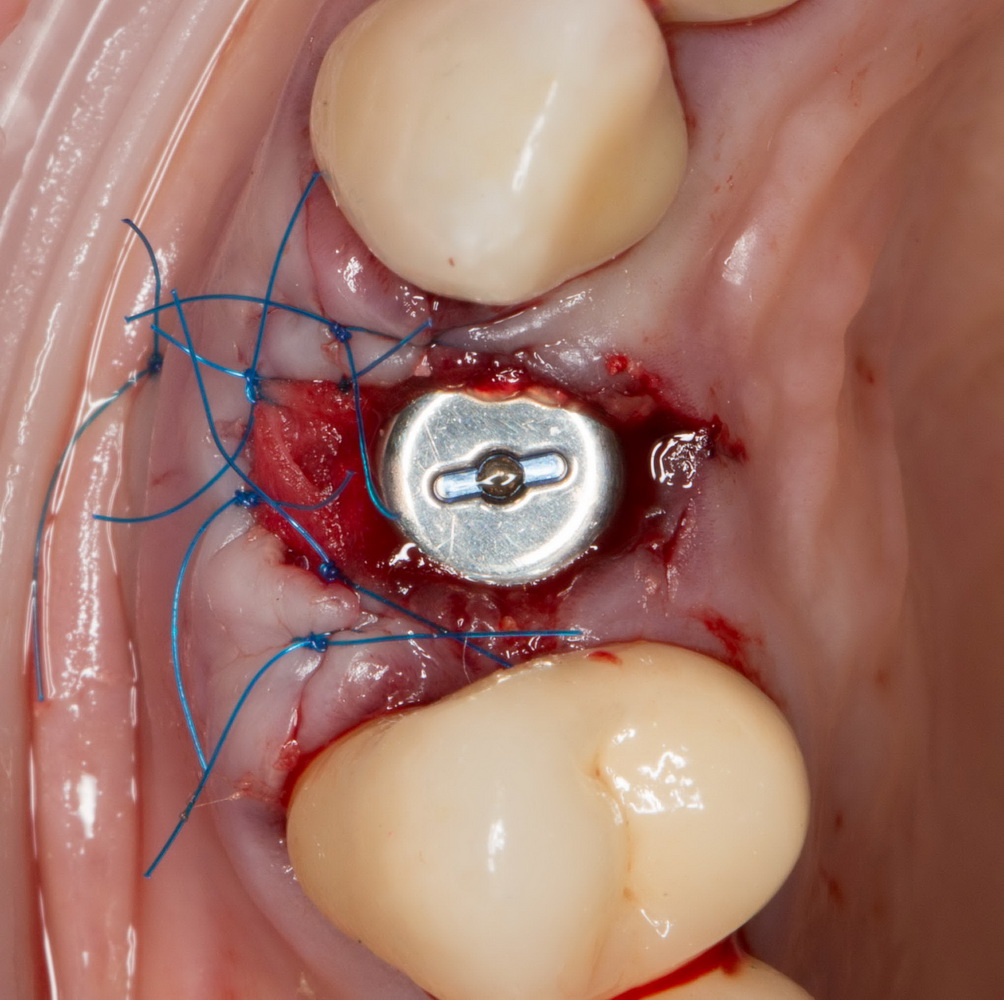

Итак, накладывается Mucograft Seal. Также успешно можно использовать любую коллагеновую матрицу любого размера:

Он подшивается узловыми швами. Операция закончена. Вид послеоперационной раны:

или вот:

У меня не было полной уверенности в том, что всё пойдет нормально, поэтому мы решили повременить с установкой коронки на имплантат до полного заживления раны, а это, примерно, несколько недель. Пациентка не против.

На следующий день послеоперационная рана выглядит следующим образом:

или вот так:

Другими словами, всё в порядке.